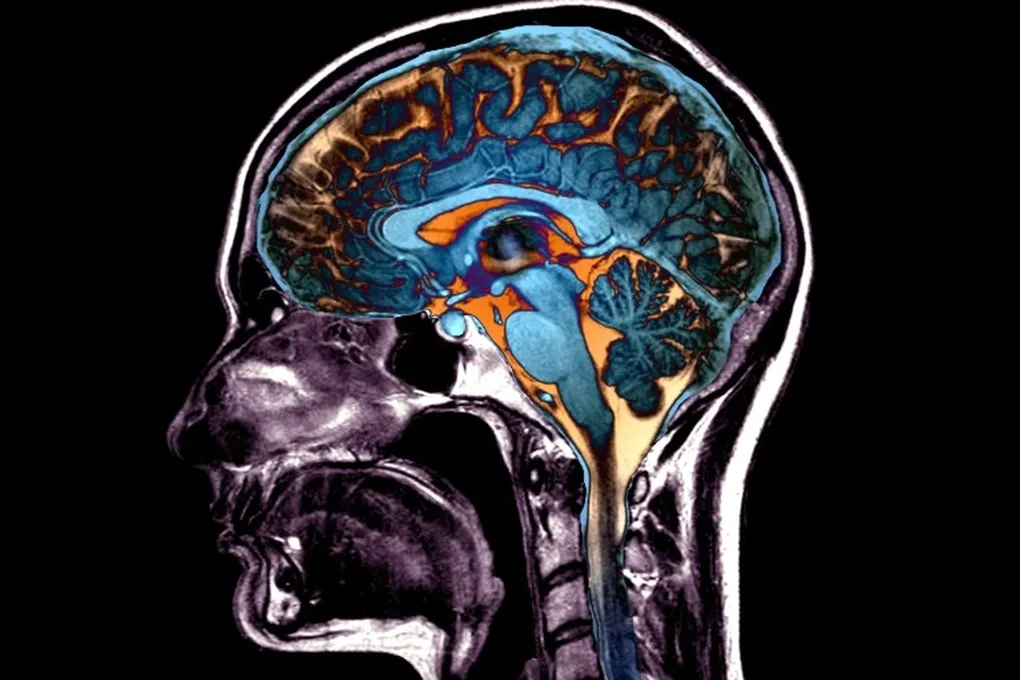

Старение меняет не только кожу. Мозг тоже теряет объём, некоторые его области как бы усыхают. Но эти изменения коварны — они микроскопические. «Человеческий глаз просто не способен уловить такие системные закономерности», — признаётся соавтор исследования Христос Давацикос. Нужен был новый, более зоркий «взгляд».

Команда использовала специально разработанный сложный алгоритм, который сначала обучили на снимках мозга как здоровых молодых людей, так и пожилых, включая тех, у кого уже начались когнитивные проблемы. По сути, алгоритм научили видеть, какие области мозга стареют «хором», а какие — по отдельности. Это позволило создать внутреннюю карту типичных возрастных изменений.

Затем эту карту наложили на снимки почти 50 тысяч человек из различных биобанков и исследований. Так и проступили пять различных сценариев, по которым мозг может терять свою субстанцию.